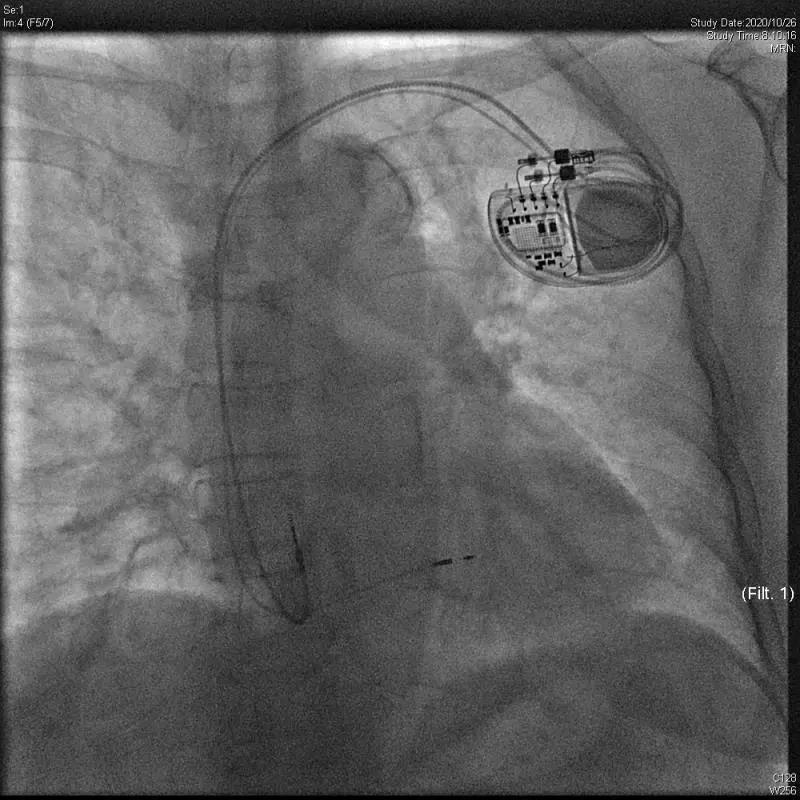

北京清华长庚医院10月26日电(心脏内科 刘元伟 何榕)10月26日,北京清华长庚医院心内科何榕医师、刘元伟医师带领团队,在副院长张萍教授的指导下,顺利植入了全国首台3.0T核磁兼容长寿命新型双腔起搏器(Astra)。

该患者为70岁女性,因III度房室传导阻滞、头晕、黑曚入院,心室率仅30-40次/分。同时伴有双手震颤、麻木、腔隙性脑梗、骨关节病等,后期明确有3.0T场强MRI检查的需求。另外,患者高龄,要求植入长寿命起搏器以减少后期器械更换次数,降低感染风险。正值3.0T长寿命起搏器刚刚进入国内,综上考虑选择植入Astra双腔起搏器。此外,患者为III度房室传导阻滞,心室起搏依赖,为避免长期右室起搏导致心功能不全,决定采用国际先进的左束支区域起搏技术。

手术过程顺利,术后起搏心电图QRS时限仅112ms,患者症状即刻缓解,手术效果良好。